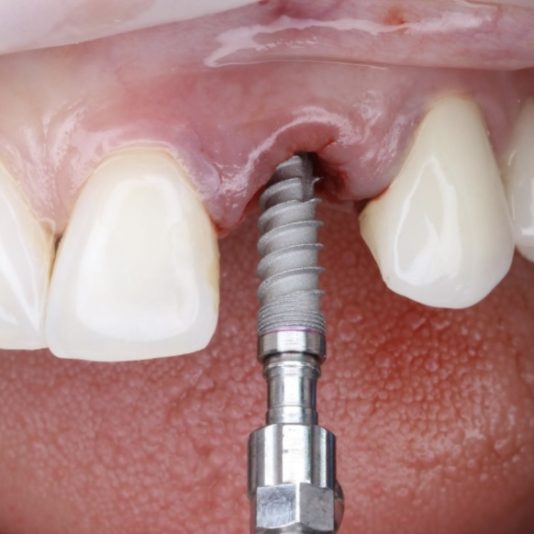

When placing implants, taking a PA X-ray of the pilot drill is a crucial step that’s often overlooked. This simple check can save you from a lot of headaches down the line.

The pilot drill sets the foundation for the entire implant trajectory. If the angulation is even slightly off at this stage, it can result in improper placement, bone perforation, or aesthetic challenges, especially in the anterior region.

By taking a PA X-ray after placing your pilot drill, you can immediately assess:

• Parallelism to adjacent teeth or implants.

• Proper alignment within the bone.